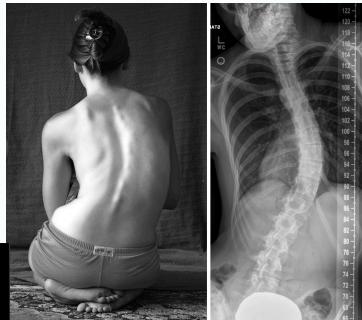

Clinical Findings

- Leaning of entire body to one side

- Head not centered directly above the pelvis

- Shoulders at different heights

- One shoulder blade more prominent than the other

- Rib cages at different heights (due to vertebral rotation)

- Uneven waist

- Raised, prominent hip

- Curve increases on forward flexion

- Compensatory scoliosis disappears on flexion

Clinical Features

- Shoulders at different heights – one shoulder blade more prominent

- Rib cages at different heights

- Skin texture changes overlying the spine